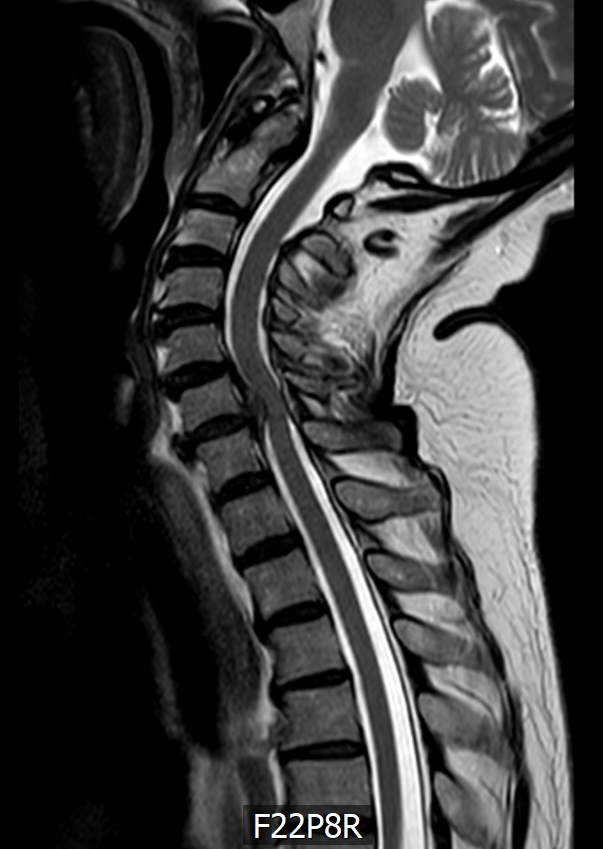

Das MRT zeigt eine 78 jährige Patientin. Schon seit Jahren klagt sie immer wieder über Nackenschmerzen. Seit einem halben Jahr hat sie ein Taubheitsgefühl in beiden Händen. Die Feinmotorik hat deutlich nachgelassen. So ist das Schliessen eines Hemdknopfes und dass Sticken nicht mehr möglich. Das Schriftbild ist kaum noch leserlich. Das Gehen ist sehr unsicher, vor allem bei Dunkelheit und auf unbekanntem Gelände.

Im MRT der HWS sieht man eine Einengung des Spinalkanals in Höhe des 6. und 7. Halswirbelkörpers. Im Spinalkanal verläuft das Rückenmark (dunkelgrau). In der Höhe der Stenose/Bandscheibenvorfalls  zeigt sich ein weisser Fleck innerhalb des Rückenmarkes. Das ist die „Myelopathie“ eine Schwellung bzw. Verletzung des Rückenmarkes aufgrund des Druckes.

Das 2. MRT Bild zeigt die Erweiterung und Entlastung des Kanals nach OP.

Im 3. Bild sieht man die Schrauben, Platte und Cage Stabilisierung in der Höhe HWK 6/7 zur Entlastung und Stabilisierung des Spinalkanals.

Direkt nach der OP waren die Beschwerden erst mal unverändert. Das Rückenmark braucht sehr viel Zeit, um sich zu erholen. Nach 6 Monaten (Zeitpunkt des 2. MRT Bild) war die Symptomatik gebessert aber immer noch nicht vollständig zurückgebildet.